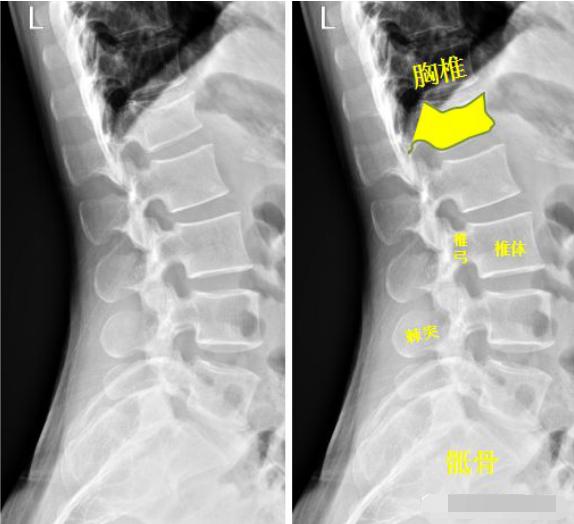

脊柱

患者洗澡摔倒,腰部着地,拍片如下:

腰椎侧位示:第1腰椎呈前低后高楔形改变,腰椎第1椎体陈旧性压缩性骨折。